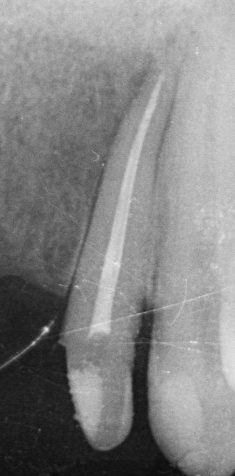

A fenti röntgenképeken egy korábban elhalt, “gócos” fog gyökérkezelés utáni gyógyulásának pillanatképei láthatóak. 1. gyökértömés pillanata 2. négy hónappal később 3. tíz hónnapal a gyökétömés után. Jól kivehető, hogy a gyökércsúcs körüli “fekete folt” fokozatosan “kifehéredik”, azaz a gyulladástól elpusztult csont visszaépül.

Amennyiben a gyökércsatornában lévő baktériumok eltávolításra kerülnek és a csatornarendszert hermetikusan zárjuk, jó esély kínálkozik a szervezet számára, hogy a bacik okozta észrevétlen gyulladás mérete fokozatosan csökkenjen majd megszűnjön. A létrejött csontdefektust 1-2-3 év alatt reparálódik, az elpusztult csont visszaépül.